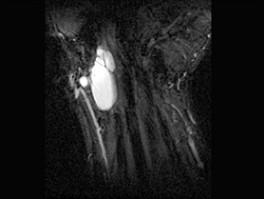

问题 男,69岁,腕部肿块1年,结合 图像,最可能的诊断是 ( )

选项 A、肌内脂肪瘤 B、未见异常 C、腕部腱鞘脓肿 D、腱鞘巨细胞瘤 E、腕部腱鞘囊肿

答案 E